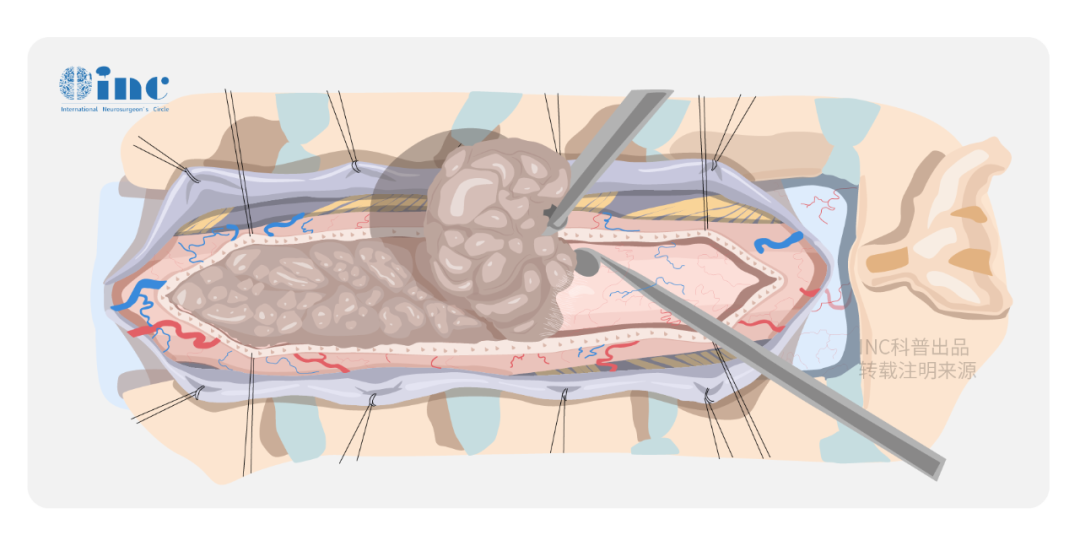

脑动静脉畸形(bAVM) 就像大脑里的不定时炸弹, 手术切除畸形团是减少出血风险并改善患者生活质量的主要方式,可手术风险有多大?要如何评估? 传统评估主要看畸形团大小、位置是否关键等。...